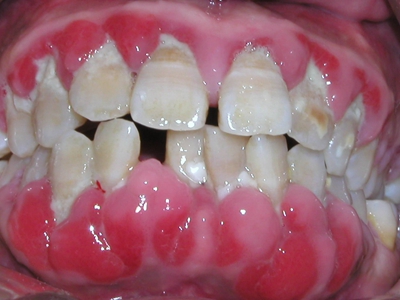

慢性龈炎的病损部位一般局限于游离龈和龈乳头,以前牙区为主,尤其以下前牙区最为显著,患者常因刷牙或咬硬物时牙龈出血而就诊。游离龈和龈乳头颜色变为鲜红或暗红色,病变较重时炎性充血可波及附着龈。龈缘变厚,龈乳头圆钝肥大,可增生呈球状,覆盖牙面。牙龈松软脆弱,缺乏弹性。

当牙龈以增生性反应为主时,龈缘和龈乳头呈坚韧的实质性肥大,质地较硬而有弹性。龈沟液量增多,还可能出现龈沟溢脓现象。